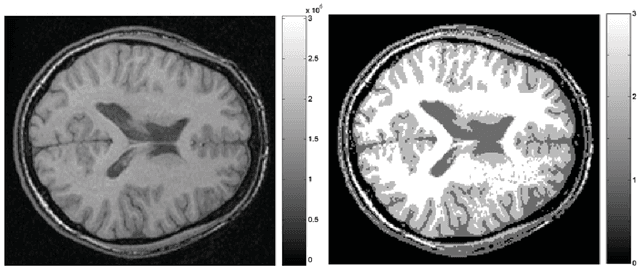

Abstract:Image acquisition and segmentation are likely to introduce noise. Further image processing such as image registration and parameterization can introduce additional noise. It is thus imperative to reduce noise measurements and boost signal. In order to increase the signal-to-noise ratio (SNR) and smoothness of data required for the subsequent random field theory based statistical inference, some type of smoothing is necessary. Among many image smoothing methods, Gaussian kernel smoothing has emerged as a de facto smoothing technique among brain imaging researchers due to its simplicity in numerical implementation. Gaussian kernel smoothing also increases statistical sensitivity and statistical power as well as Gausianness. Gaussian kernel smoothing can be viewed as weighted averaging of voxel values. Then from the central limit theorem, the weighted average should be more Gaussian.